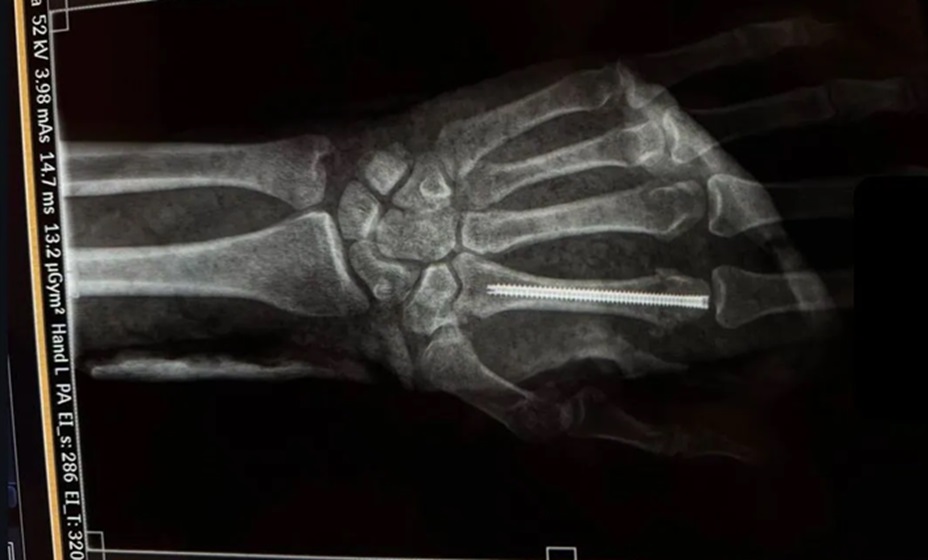

Умару Нурмагомедову вставили штифт в кисть левой руки после боя с Двалишвили. Фото: соцсети Умара Нурмагомедова

Российский боец ММА Умар Нурмагомедов получил перелом в поединке с чемпионом UFC в легчайшем весе Мерабом Двалишвили.

Уроженец Дагестана выложил фотографию в соцсети, из которой понятно, что спортсмену вставили штифт в кисть левой руки.